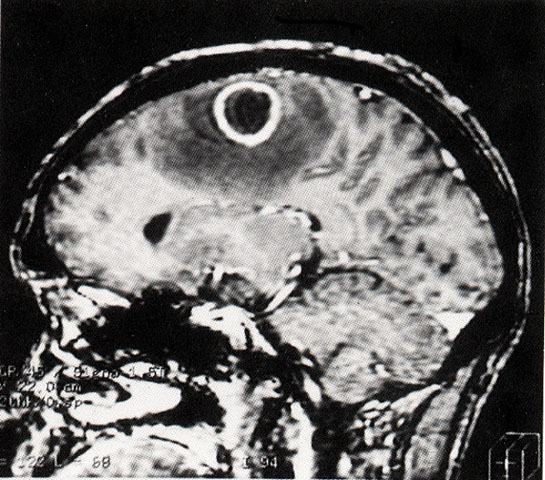

FH1048 脑脓肿(MRI)

图  名 脑脓肿(MRI)